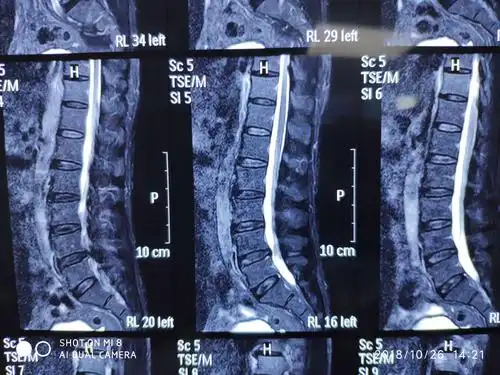

大通道脊柱内镜下经椎板间隙单侧入路双侧减压技术治疗腰椎管狭窄症

术前ct显示横断面椎管严重狭窄

磁共振显示椎管狭窄明显